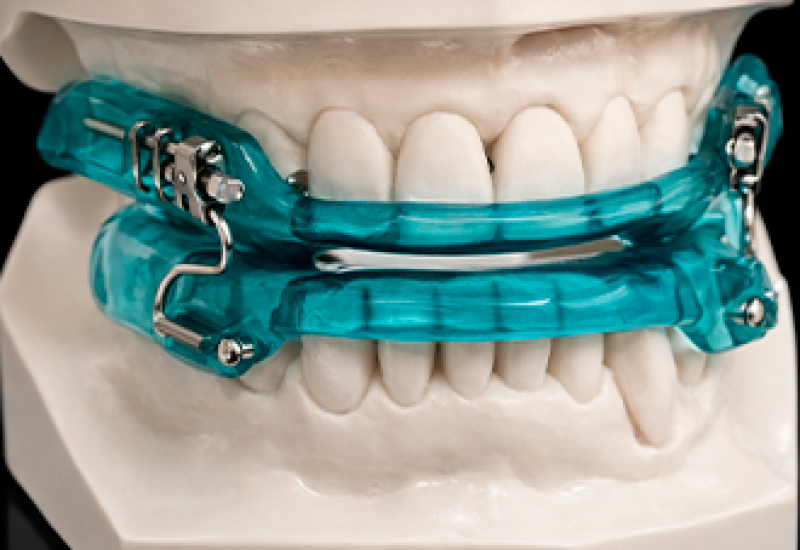

Ortopedia Funcional dos Maxilares